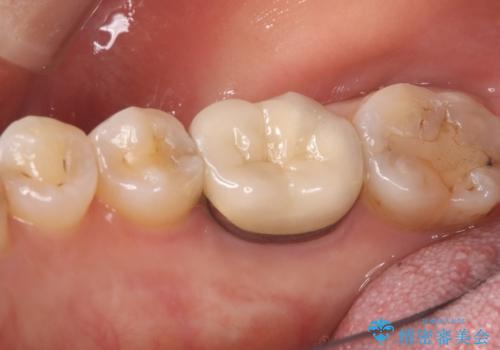

クリーニングにいらした患者さんで、右下7番目の歯の奥側の面や手前の歯との間にう蝕があり、噛む面にも蝕処置によるレジン材料が詰まっていたことから、う蝕も古い材料も全て除去しセラミックインレーでのやり替えとなりました。

右下7近遠心にカリエスを認め、咬合面のCR修復も劣化していたので、カリエスと古い材料を全て除去し新しくCR裏層した後、セラミックインレーをセットしています。セット時はラバーダム防湿を行っています。